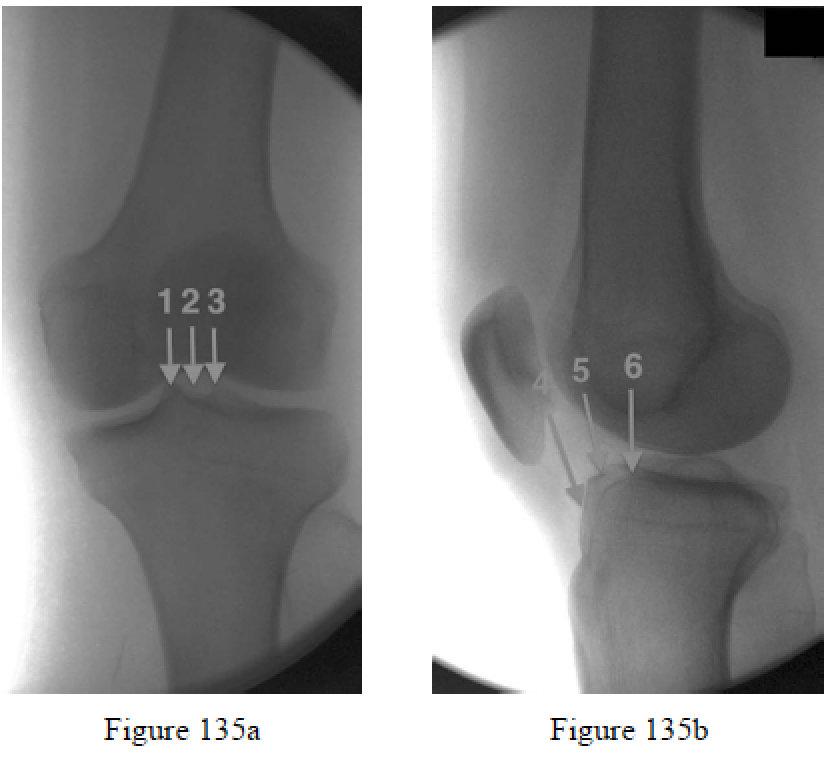

Walker RM, Zdero R, McKee MD, Waddell JP, Schemitsch EH. Ideal tibial intramedullary nail insertion point varies with tibial rotation. J Orthop Trauma. 2011 Dec;25(12):726-30. doi: 10.1097/ BOT.0b013e31821148c7. PubMed PMID: 21886003.

McConnell T, Tornetta P 3rd, Tilzey J, Casey D. Tibial portal placement: the radiographic correlate of the anatomic safe zone. J Orthop Trauma. 2001 Mar-Apr;15(3):207-9. PubMed PMID: 11265012.